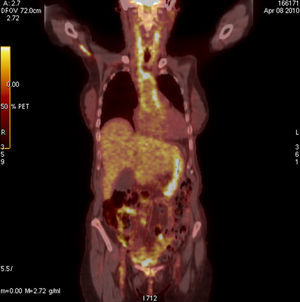

Caso clínico 2Mujer de 74 años con dolor y debilidad en cintura escapular y pelviana, con rigidez matutina de más de una hora de duración y elevación de los reactantes de fase aguda. Ante la sospecha de polimialgia reumática (PR) se administraron glucocorticoides a dosis de 30mg/día de prednisona con mejoría inicial, pero con rápida recurrencia de los síntomas y con deterioro analítico en el que destacaba una hemoglobina de 8mg/dl, PCR de 19mg/dl y VSG de 120mm en la primera hora. La paciente no refería clínica local craneal como cefalea, claudicación mandibular o dolor a la palpación de la arteria temporal y los pulsos periféricos eran normales. Ante la sospecha de neoplasia se realizó analítica con marcadores tumorales, TAC toracoabdominal, gastroscopia y colonoscopia, todo ello con resultados normales, se completó el estudio, finalmente, con la realización de un PET-TAC (fig. 2) que informó de proceso vasculítico en Ao, tronco braquiocefálico, carótidas y subclavia. Ante la firme sospecha de ACG se realizó biopsia de arteria temporal no guiada por ecografía, que confirmó el diagnóstico.